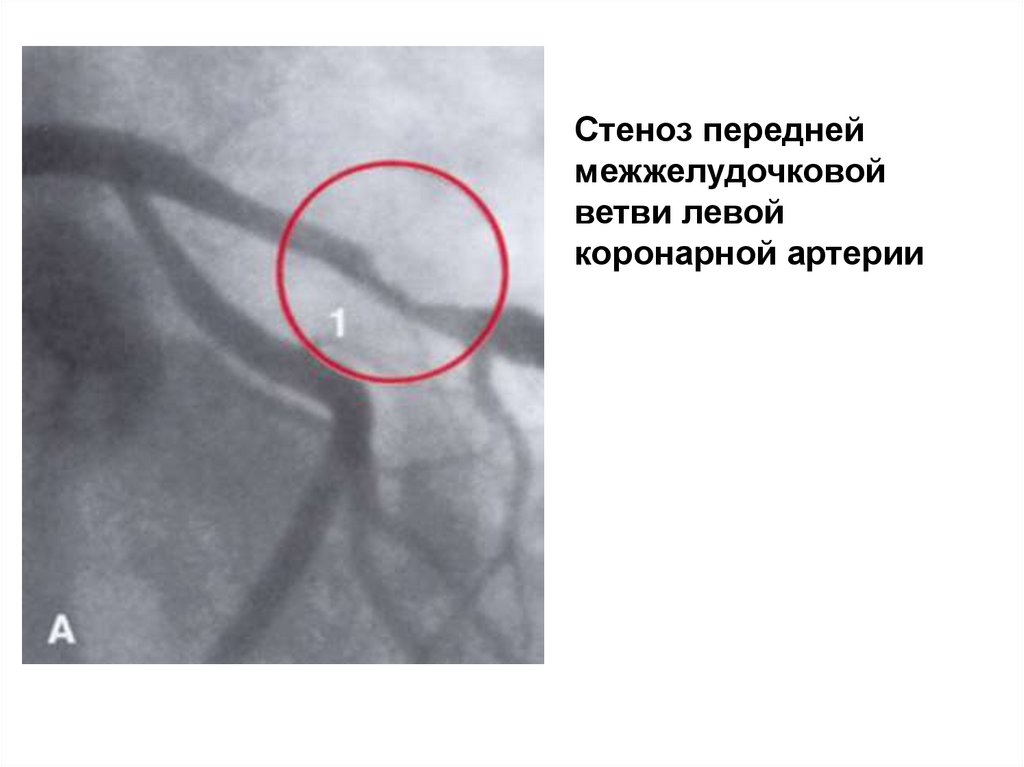

Стеноз передней

межжелудочковой

ветви левой

коронарной артерии